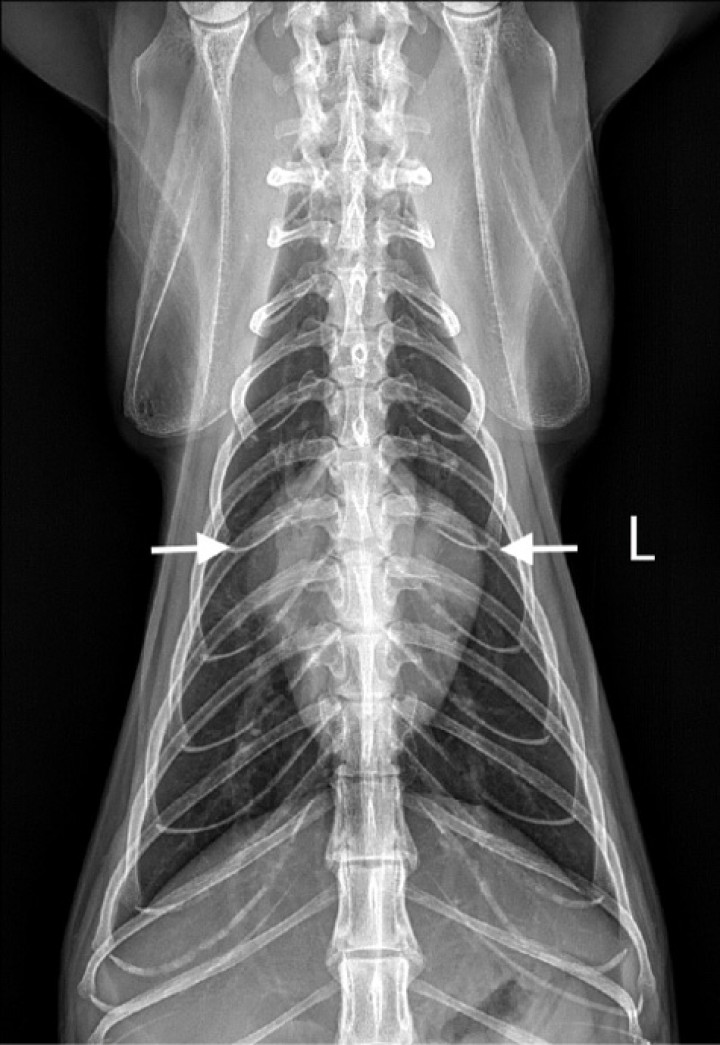

<p>Radiografía dorsoventral (DV) de tórax de un gato con cardiomiopatía hipertrófica. Se observa un ensanchamiento de la región de la base cardiaca (flechas blancas), adquiriendo una imagen denominada de “corazón de San Valentín”.</p>

Figura 4

Radiografía dorsoventral (DV) de tórax de un gato con cardiomiopatía hipertrófica. Se observa un ensanchamiento de la región de la base cardiaca (flechas blancas), adquiriendo una imagen denominada de “corazón de San Valentín”.